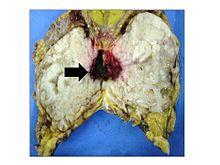

Anatomopathological results of phyllodes tumor.